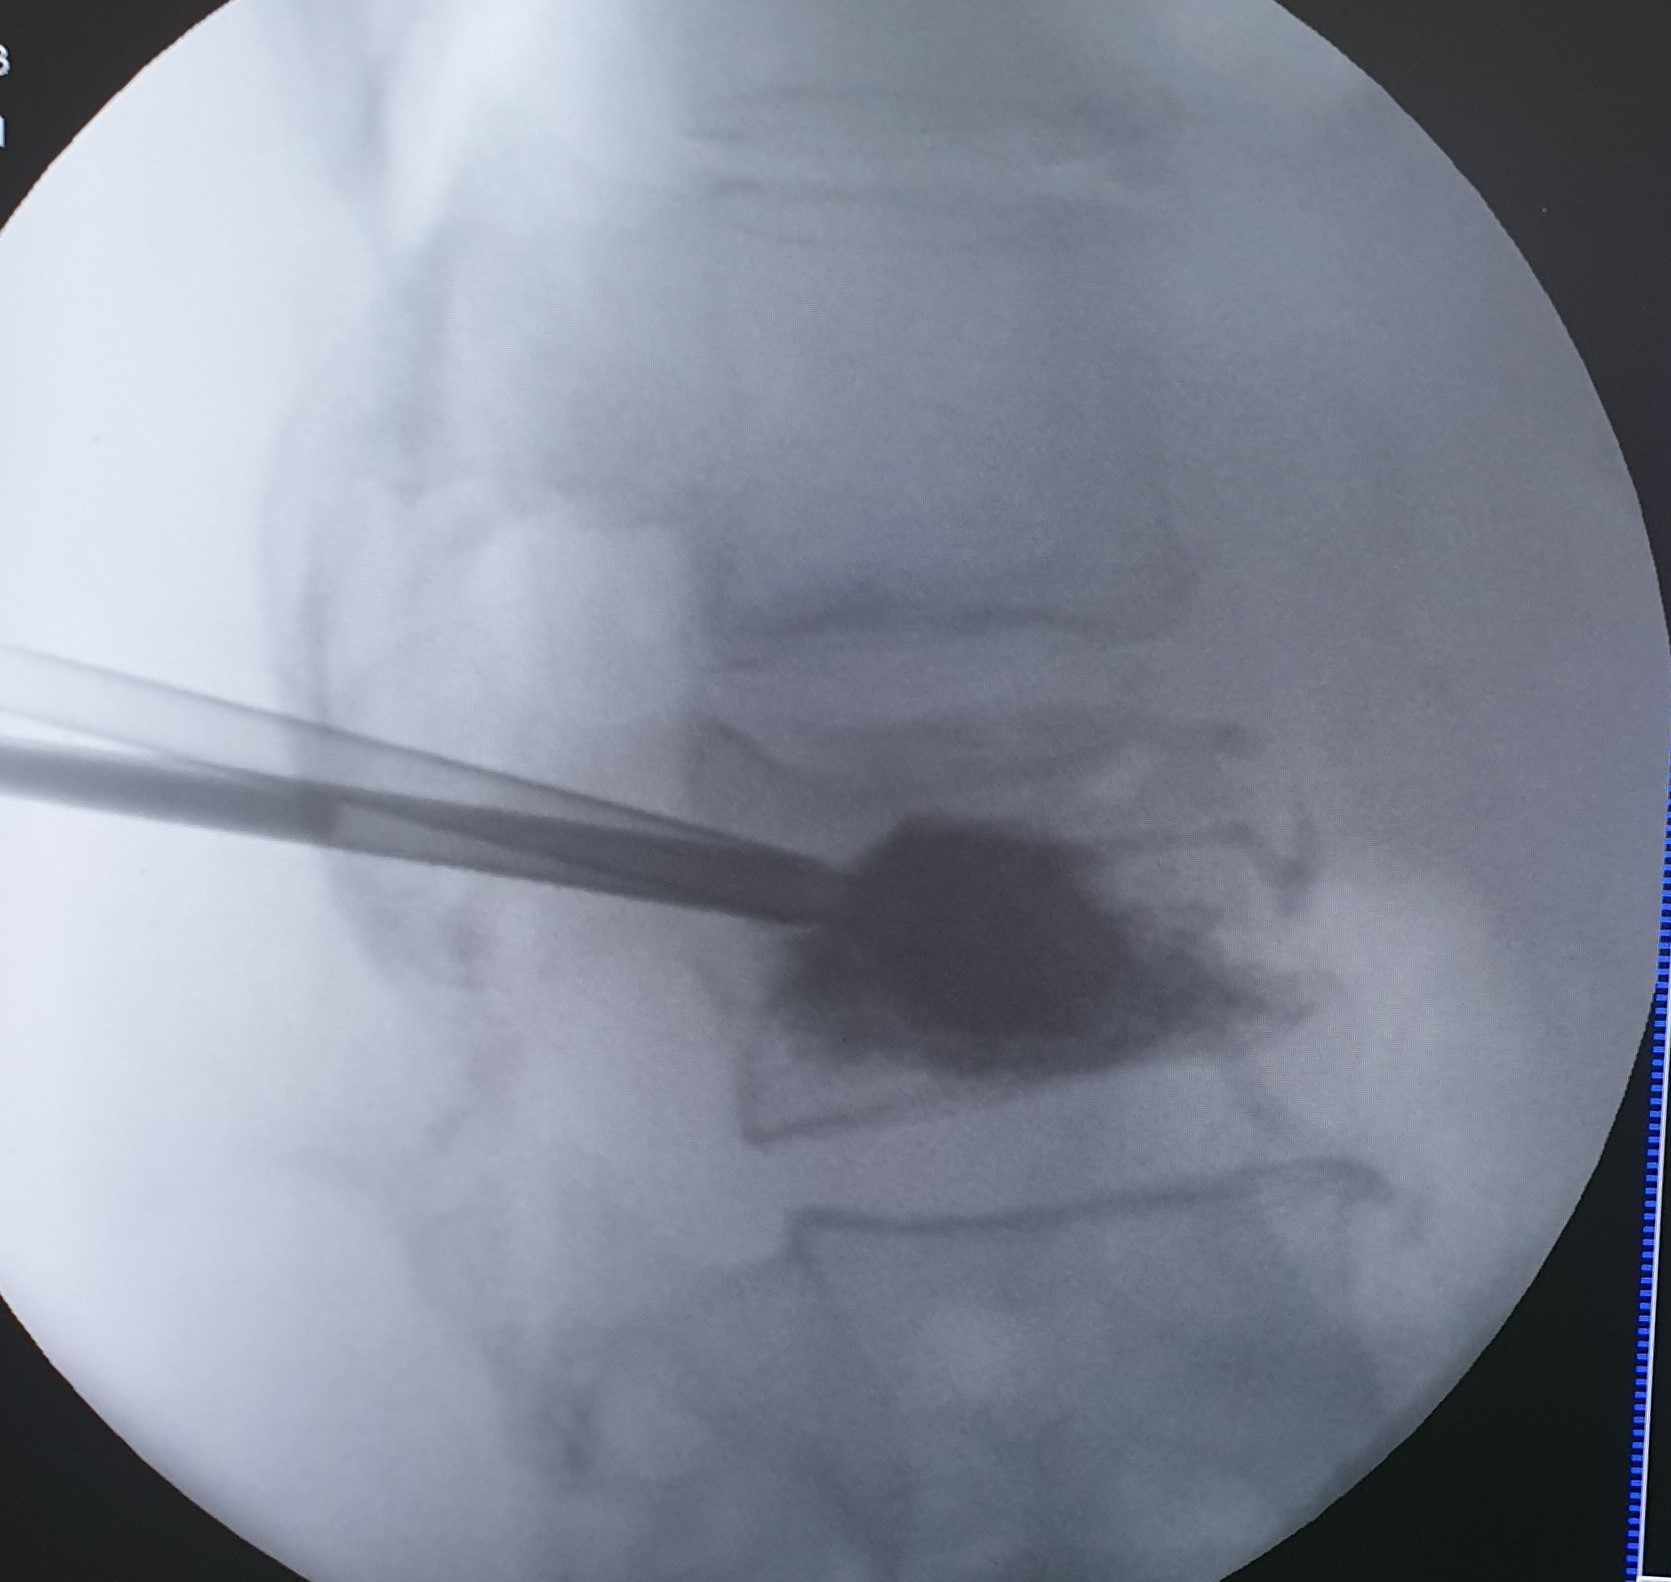

- Κυφοπλαστική και σπονδυλοπλαστική